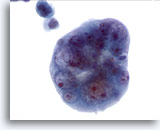

Figure 68

Lymph node FNA, atypical lymphoid proliferation.

The specimen is cellular and when compared to small lymphocyte a the majority of cells are slightly larger than this cell. The monotony of the sample is worrisome. 20x

Lymph node FNA, atypical lymphoid proliferation.

The specimen is cellular and when compared to a small lymphocyte the majority of cells are slightly larger than this cell. The monotony of the sample is worrisome.

20x